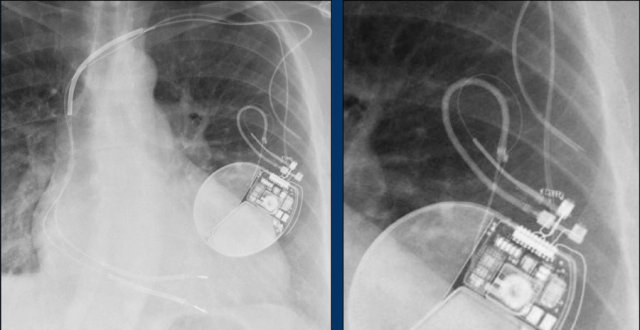

Here an example of an ICD with wires in the right atrial appendage, the apex of the right ventricle and a lead to the left ventricle in the posterior coronary vein.

You can recognize the two shock coils of the ICD as thicker white bands along the course of the lead.

Here a biventricular pacemaker with three leads.

The right atrial pacemaker lead is located in the atrial appendage.

This lead first travels inferiorly into the right atrium and then turns upward and anteriorly where it is anchored within the trabeculae of the atrial appendage.

The left ventricular lead travels through the right atrium and the sinus coronarius and is finally positioned posteriorly into a cardiac vein on the left.